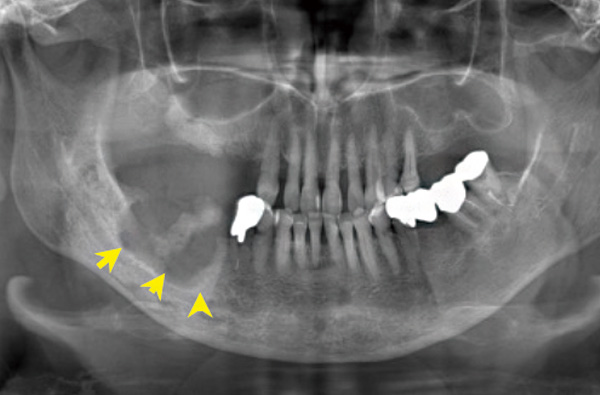

下顎前歯と左下に骨露出あり。

CTでは広範囲の鼻腔と交通する瘻孔(矢印)と下顎下縁に至る腐骨形成(矢印)が確認されます。